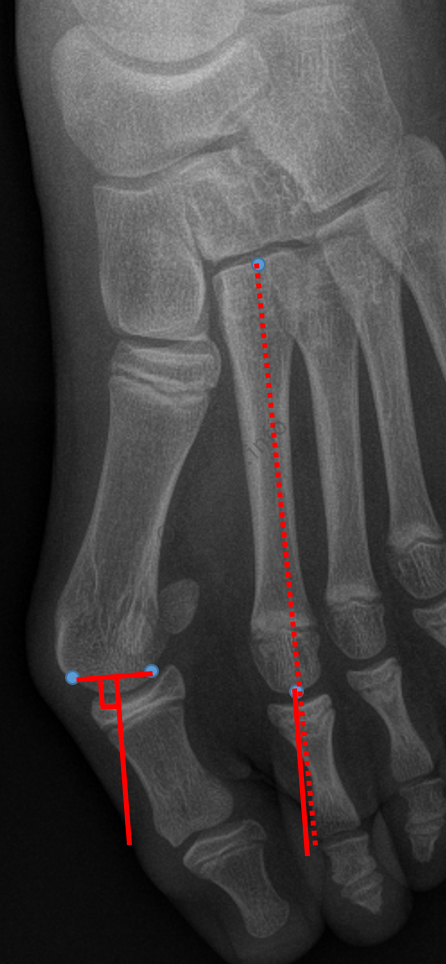

Angle métatarso-phalangien du 5ème rayon

- Angle formé par les axes du métatarsien et de la première phalange du cinquième rayon

- Normal : 8-10°

Angle inter-phalangien du 1er rayon

- Angle entre les deux premières phalanges de l’hallux

- Normal : 13°